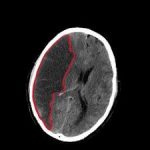

Existen dos tipos de ACV: el isquémico, que representa el 80% de los casos y sucede cuando hay una obstrucción en un vaso sanguíneo cerebral. El otro tipo es el hemorrágico, que representa el 20%, y es ocasionado por la ruptura de un vaso sanguíneo.

Isquémico

Hemorrágico